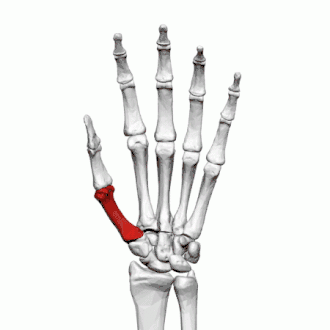

Fractures

Les fractures des os métacarpiens représentent 30 à 40 % de toutes les fractures de la main, dont 25 % surviennent dans le premier métacarpien (deuxième après les fractures du cinquième métacarpien) et 80% des fractures du premier métacarpien surviennent à sa base[2].

Les fractures courantes du premier métacarpien sont la fracture de Bennett et la fracture de Rolando.

La fracture des quatrième et cinquième métacarpien est fréquente après un coup de poing : fracture du boxeur.